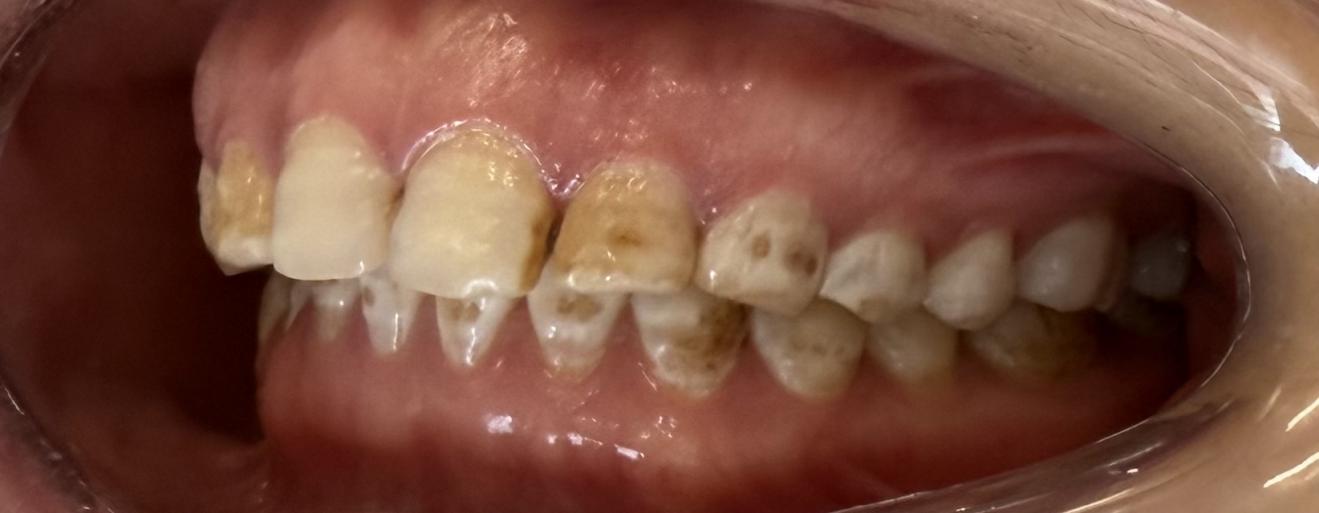

当日,患者前来复诊,戴入最终修复体后,她看着镜中整齐洁白、形态自然的前牙,感觉像换了一副新牙齿!患者表示,咀嚼功能明显改善,公共场合也敢张口大笑了,对医生的精心诊治表示感谢。